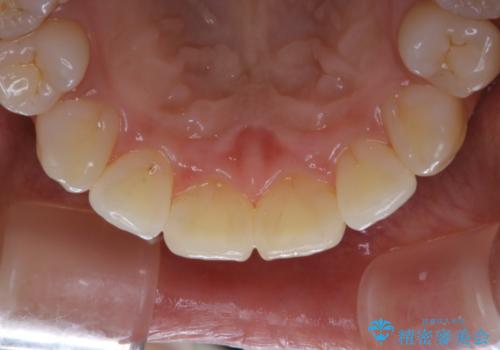

定期的なメンテナンスをして頂いていること、ご自身でのケアをかなり丁寧にされていていることで、歯石や着色の量がさほど多くなかったため30コースで全体的なクリーニングが可能でした。

矯正治療が終了した後は、歯並びの改善により歯ブラシやフロスが通しやすくなります。ただし、日々の磨き残しや唾液の成分などによりバイオフィルムや歯石はどうしても付着してしまいます。そのため、2~3か月に1回は、歯科医院での専門的クリーニングをすることが大切です。